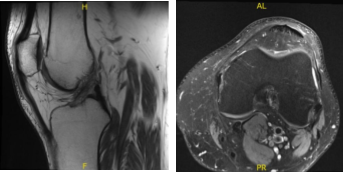

MRI-3T Left Knee Non-contrast

After a few months the patient visited for a follow up and presented the results of his MRI and shown signal alteration the posterior horn medial meniscus may represent a site of primary repair of the medial meniscus tear. Correlate with surgical history. No new tear is visualized. Trace joint effusion. Small quadriceps enthesophyte.

MRI-3T Left Knee Non-contrast